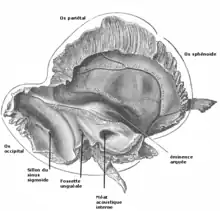

L'os temporal est un os pair du crâne situé dans la région de la tempe, sur la partie latérale de la tête. Il participe à la formation de la voûte de la base du crâne. Il accueille aussi l'articulation temporo-mandibulaire, les organes de l'audition avec la caisse du tympan et de l'équilibre avec le vestibule et la cochlée.

Son anatomie est réputée une des plus complexes de tous les os du corps humain et on peut l'aborder sous plusieurs perspectives : du point de vue de ses faces endocrânienne et exocrânienne et de ses quatre bords, ou du point de vue de ses composantes issues plus ou moins de ses origines embryologiques.

L'os temporal résulte de la fusion de trois os qui se soudent dans l'adolescence : l'os squamosal, l'os tympanal et l'os pétreux qui gardent comme trace de séparation un fin sillon sur la surface de l'os. Mais on a l'habitude pour le décrire de le séparer en trois parties qui ne correspondent pas à la formation de l'os. C'est ainsi qu'on distingue :

Face endocrânienne

Elle se divise en une partie squameuse antérieure faisant partie de l'écaille de l'os temporal, une partie pétreuse et une partie mastoïdienne postérieure.

Partie squameuse

La partie squameuse est concave et marquée par des sillons correspondant aux empreintes des branches de l’artère méningée moyenne et des empreintes correspondant aux circonvolutions du lobe temporal. Elle est limitée en bas par le vestige de la suture pétro-squameuse supérieure issu de la fusion de l'os squamosal et de l'os pétreux.

Partie pétreuse

La partie pétreuse est en forme de pyramide quadrangulaire oblique en avant et en dedans. Elle présente deux faces endocrâniennes et deux faces exocrâniennes.

Face antéro-supérieure endocrânienne

La face antéro-supérieure endocrânienne (ou rostrale ou cérébrale) se situe dans la fosse crânienne moyenne. Elle est limitée entre le bord supérieur de la pyramide pétreuse et par la fissure pétro-squameuse, vestige de la fusion entre l'os pétreux et l'os squamosal.

Le toit du canal semi-circulaire supérieur marque un relief en arrière : l'éminence arquée et en avant le toit de la cavité tympanique crée le tegmen tympani.

À l'avant apparait le hiatus du canal du nerf grand pétreux et le hiatus du canal du nerf petit pétreux. À l'avant de ces hiatus, l'empreinte trigéminale logeant le cavum de Meckel.

Face postéro-supérieure endocrânienne

La face postéro-supérieure endocrânienne se situe dans la fosse crânienne postérieure. Elle est limitée par le bord supérieur et le bord postérieur de la pyramide pétreuse.

Elle est perforée par le méat acoustique interne passage du nerf facial et du nerf vestibulocochléaire.

Au-dessus et en arrière se trouve la fossa subarcuata qui s'ouvre sur le canalicule vestibulaire. Encore en arrière le foramen de l'aqueduc du vestibule.